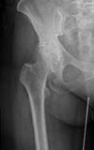

Koxarthrose

​Die Koxarthrose ist der Fachbegriff für die Abnutzungserscheinung des Hüftgelenkes. Typische klinische Zeichen sind das Auftreten von Schmerzen in der Leiste bis zum Knie sowie Bewegungseinschränkungen. Bei entsprechender Indikation erfolgt als operative Möglichkeit die Implantation einer Hüfttotalendoprothese (HTEP).

Hierbei handelt es sich um den Ersatz von Hüftpfanne und Hüftgelenkskopf. Die Implantate werden mit oder ohne Knochenzement verankert, je nach Knochenqualität. Je nach Grad und Art der Abnutzung des Hüftgelenkes steht eine Vielzahl von Implantaten zur Verfügung. Bei Eignung des Befundes wird eine minderinvasive Operationstechnik angewandt, welche zu einer geringeren Traumatisierung des Gewebes und einer schnelleren Mobilisierung der Patienten führt.